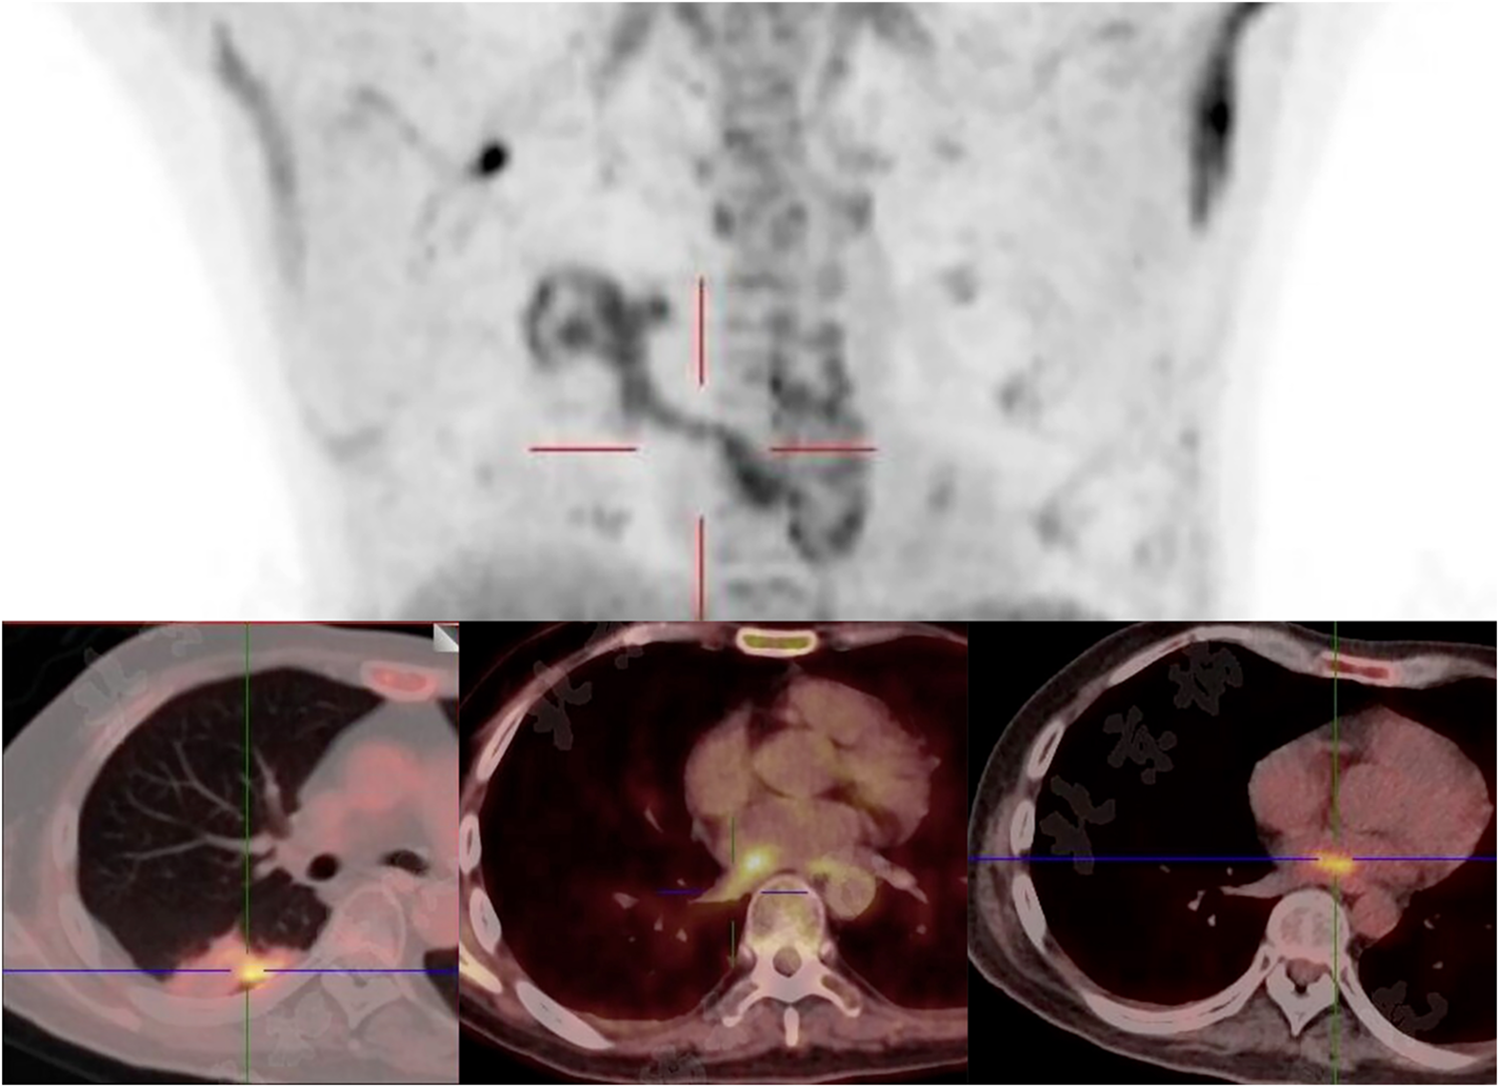

Figure 3

Focal infectious uptake was detected in the right lower lobe dorsal segment on PET/CT. The SUVmax is 5.0 in the pulmonary lesion, 5.3 in the left atiral lesion, and 4.9 in the RIPV.

Given the multiple cardiac-source septic emboli, surgical resection of the left atrial vegetation was planned for this patient. Whole-body PET/CT 1 day before surgery showed a right lower lung lobe infectious focus spreading via the RIPV to the left atrium (Figure 3), no suspected intracranial infectious foci were noted. Preoperative labs showed pancytopenia: hemoglobin 75 g/L, neutrophils 3.44 × 109/L, and platelets 26 × 109/L. Perioperative risks were minimized by component transfusion. Intraoperatively, routine cardiopulmonary bypass was established via cannulation of the ascending aorta and superior/inferior vena cava. Through an atrial septal incision, the left atrium was explored, revealing a 4 × 1 cm hyphae-like vegetation (Figure 4) extending from the RIPV into the left atrial cavity, causing complete obstruction of the RIPV. After meticulous excision of the intracardiac portion, further exploration of the RIPV demonstrated the vegetation originating from its dorsal segmental tributary. The venous part of the vegetation was carefully dissected along the RIPV and its tributaries until reaching positions beyond instrument access. Procedures were performed within the pulmonary veins without injuring the endothelium, thereby eliminating the need for pulmonary vein isolation or reconstruction. Following resection, adequate backflow bleeding was confirmed from the RIPV and its tributaries. Total bypass time was 106 min and the aortic cross clamp time was 77 min. Histopathology of the vegetation confirmed V. volvacea endocarditis (Figure 5), further verified by V. volvacea DNA PCR.